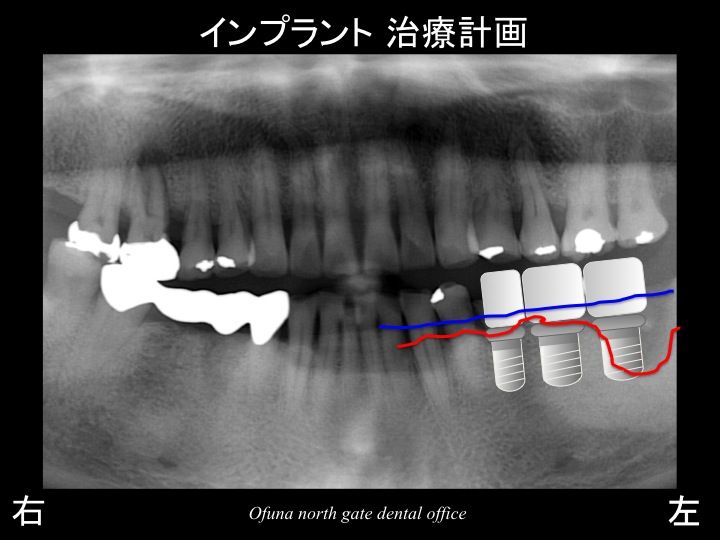

骨吸収を分かりやすくするために

骨吸収の状態を線で書いたのが以下のレントゲンになります。

青線が骨吸収を起こす前の骨の位置です。

赤線は、現在の骨の位置です。

これらの歯は、当然抜歯となります。

抜歯が遅すぎた状態です。

抜歯後、約3ヶ月待ちインプラント治療の開始となります。

骨吸収が大きいため、一番奥の部分ではインプラントをそのまま埋入することは不可能です。

インプラント埋入と同時に骨の増大治療が必要となります。

骨増大治療法とは、GBR法 のことです。